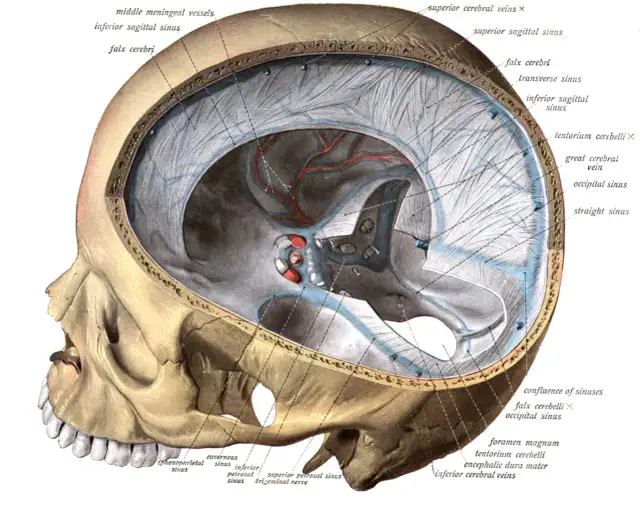

Zatoka strzałkowa górna - kluczowa rola w anatomii mózgu i zdrowiu

Zatoka strzałkowa górna odgrywa kluczową rolę w anatomii mózgu. Dowiedz się, jak wpływa na zdrowie oraz jakie patologie mogą ją dotyczyć.